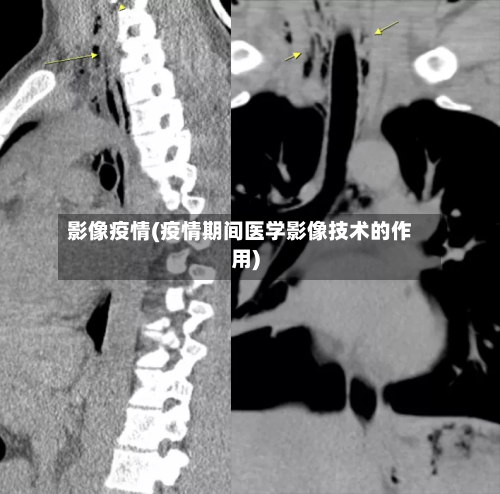

是的 ,您的CT片有可能由AI医生来读取,近来已有新冠肺炎CT影像AI筛查系统应用于医院,辅助医生进行诊断。以下是对该AI系统的详细介绍:系统研发与应用:南开大学计算机学院与北京推想科技联合研发了新冠肺炎CT影像AI筛查系统 ,该系统已在包括湖北在内的国内40家医院应用部署 。

不同医院CT导入AI读片的时间存在差异 ,具体如下:献县中医院:CT室于2023年引入并开展人工智能(AI)影像辅助诊断应用技术 。这一举措标志着该院在医学影像诊断领域迈出了重要一步,通过AI技术的辅助,能够更快速、准确地识别影像中的异常 ,为临床医生提供更可靠的诊断依据。